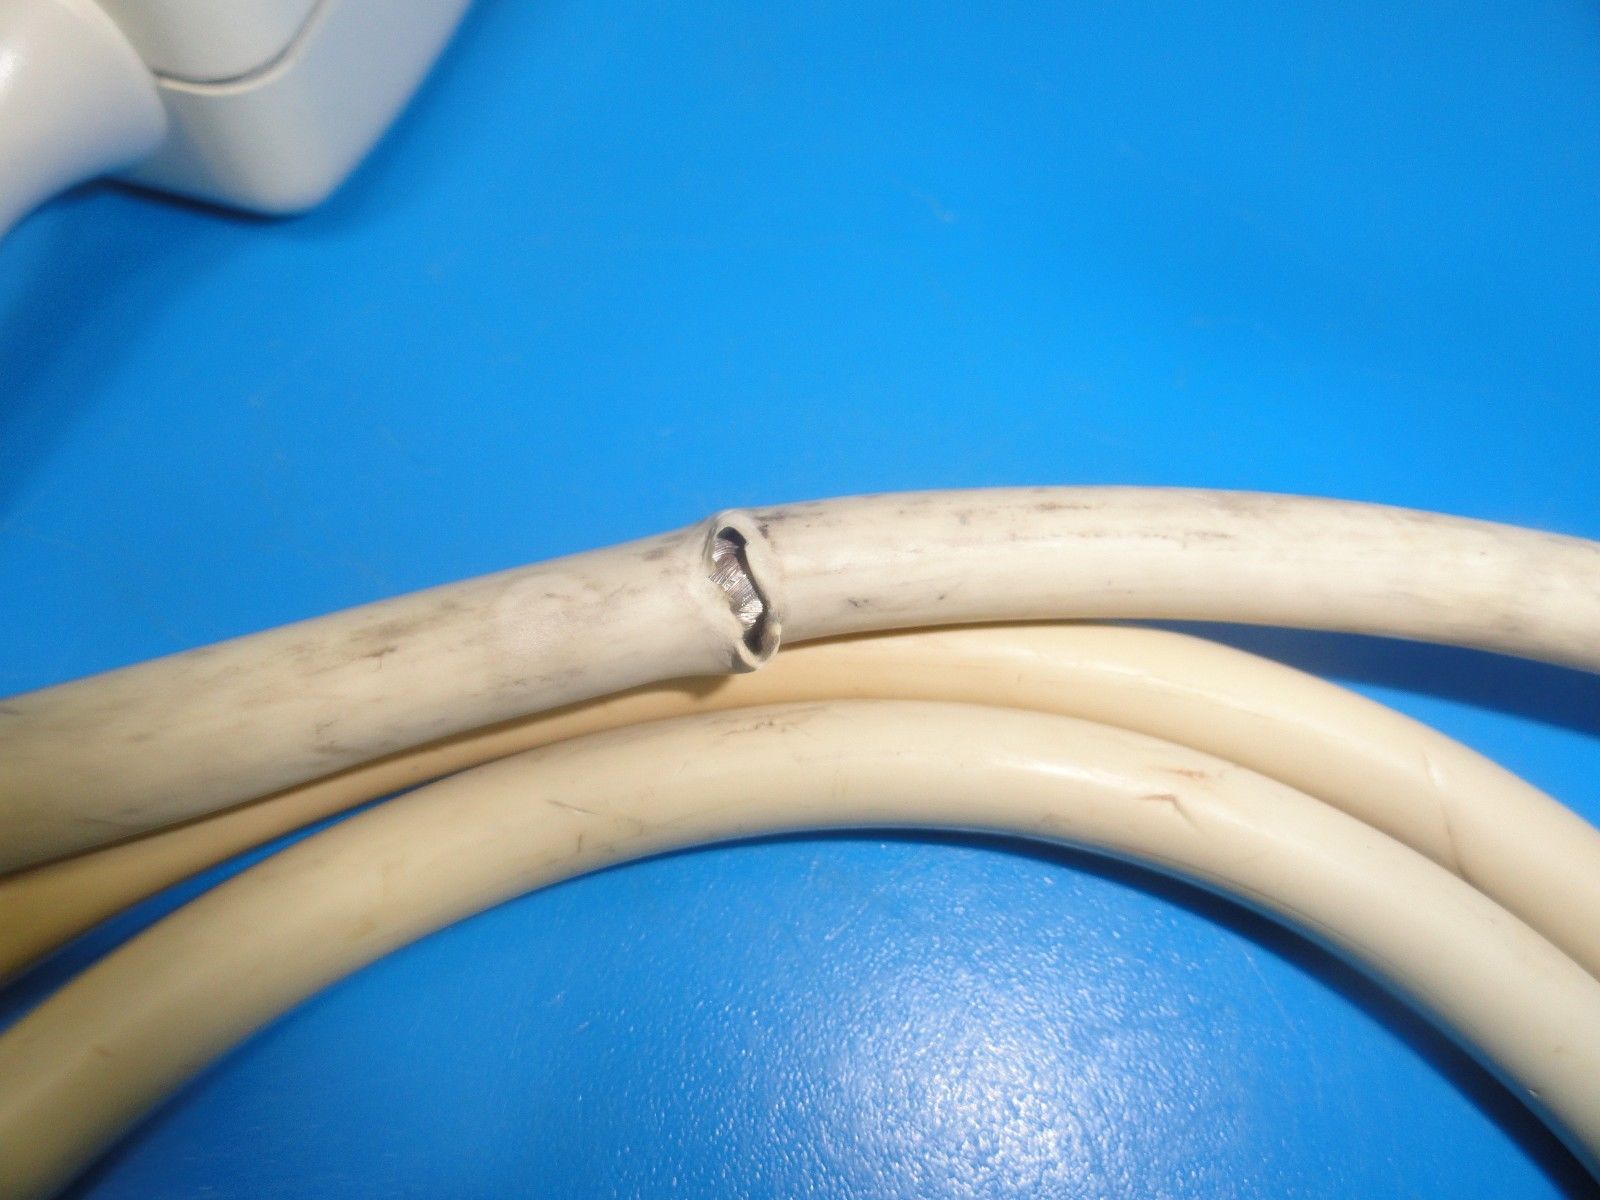

The ATL HDI C4-2 40R Curved Array Broadband Probe (6322) is a versatile ultrasound transducer designed for abdominal and OB/GYN imaging. Featuring a 4-2 MHz frequency range, this curved array probe provides excellent image clarity and depth penetration, making it ideal for imaging both superficial and deeper structures. It is particularly effective for abdominal, obstetric, and gynecological examinations, allowing healthcare professionals to capture clear images of the uterus, ovaries, and other abdominal organs. The broadband capabilities of the C4-2 40R ensure high-resolution images across a wide range of patient types and conditions, while its ergonomic design enhances comfort and ease of use during extended procedures. Compatible with the ATL HDI ultrasound systems, this probe offers seamless integration and optimal performance, helping clinicians make accurate and timely diagnoses. Whether for routine checks or more specialized exams, the ATL HDI C4-2 40R is a reliable, high-performance tool for medical imaging.